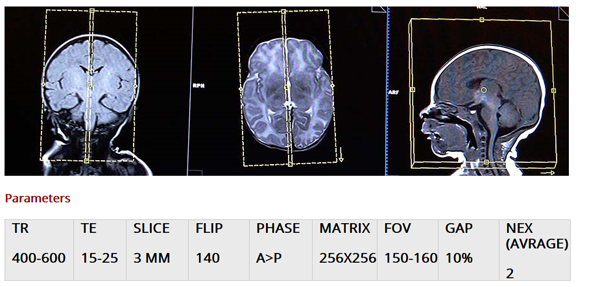

T1 tse sagittal small fov 3mm +iv

چينش کاتهاي پلان ساژيتال را بروي پلان اگزيال تنظيم ميکنيم : کاتها را موازي ميدلاين (خط وسط مغز) زاويه ميدهيم.و در  پلان کرونال کاتها را موازي خطي که از ميان بطن سوم و ساقه مغز ميگذرد تنظيم مي کنيم

اسلايسهابايستي تمام مغز را از لوب تمپورال تا لوب تمپورال ر پوشش دهد